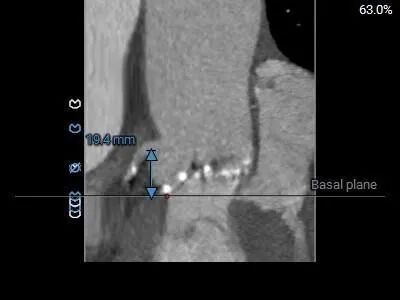

左冠19.4,右冠25.8,综合分析冠脉阻挡风险适中

瓣上多平面分析